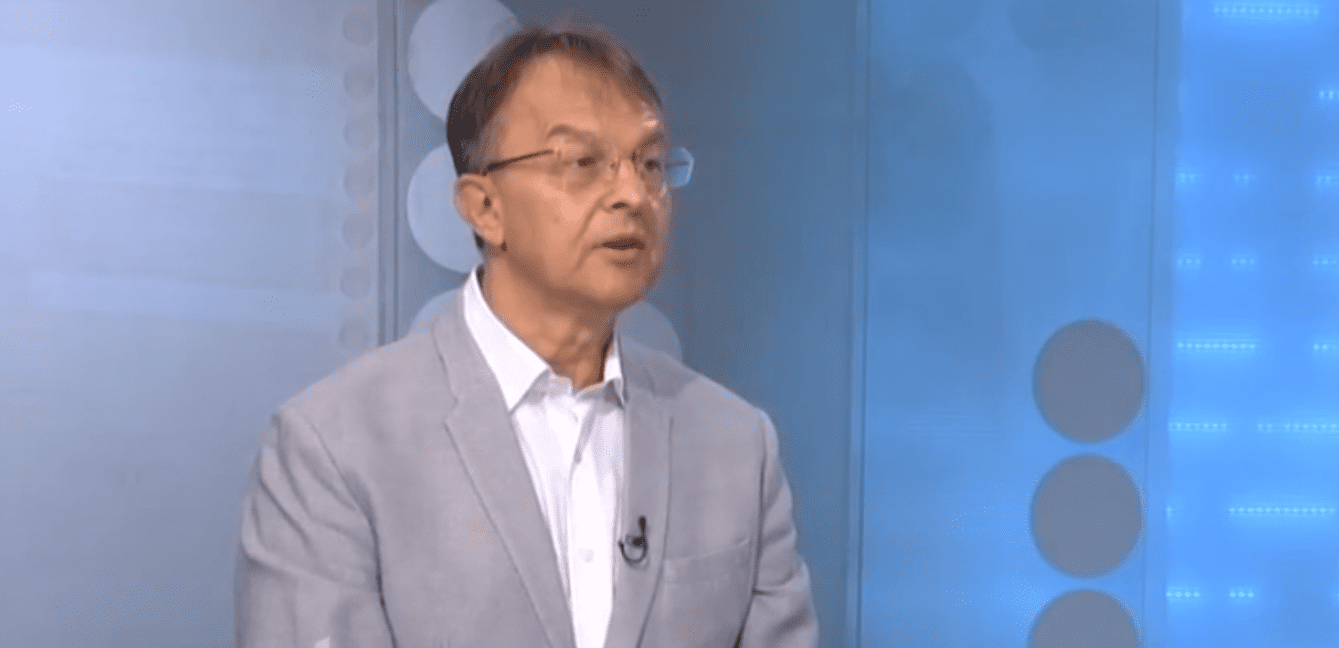

Prof. dr Vladislav Vukomanović ističe da je svaki pacijent koji je na respratoru životno ugrožen.

“Tako i u ovom slučaju 17-godišnji dečak koji je gojazan, devojčica od 15, odnosno 16 godina, bez nekih komorbiditeta i petomesečno odojče“, kaže dr Vukomanović za RTS.

Na pitanje da li je ovo prvi put da su deca na respiratoru, doktor kaže da je sada drugačiji klinički obrazac manifestacije infekcije kod dece.

„Pre samo šest meseci dominantni kada je reč o težini bolesti su bili bolesnici sa multisistemskim inflamantornim sindromom. Mi smo ih imali ovde oko 55, nešto možda i više. Svi su izlečeni i nadamo se potpuno zdravi“, navodi Vukomanović.

Ističe da se sada radi sa pacijentima sa teškim upalama pluća.

„Sva tri ova bolesnika na respiratoru imaju teške upale pluća i primljen je pre 48 sati jedan bolesnik koji ima upalu srčanog mišića i upalu srčane kese – znači raznolike i veoma teške akutne manifestacije ove bolesti“, dodaje doktor.

Kako kažu epidemiolozi, to je moguće ako se vakciniše 70 ili 80 odsto populacije. “Kada se to bude desilo onda će i kruženje virusa, pa i broj zaraženih značajno pasti, a samim tim i obolele dece“, navodi Vukomanović.

„Ono što je loša vest, da ne kažem alaramantna vest, je da deca sada ispoljavaju veoma, veoma težak oblik bolesti. Razmišljanje moje dete sigurno neće da se zarazi nije dobar način razmišljanja. Prvo roditelji vakcinišite se svi, a odobrena je i vakcinacija dece od 12 do 18 godina, posebno za ugrožene grupe bolesnika kod kojih bolest može da bude teška“, poručuje doktor Vukomanović.